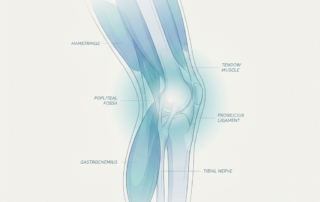

Pain Behind the Knee: The Popliteal Fossa Diagnostic Framework That Tells You Exactly What Structure Is Involved

Pain behind the knee is one of the most misdiagnosed complaints in musculoskeletal care, largely because the popliteal fossa packs multiple overlapping structures into a small space. This anatomy-first diagnostic framework helps you systematically identify which structural layer is driving your symptoms. Learn the critical red flags—including DVT-mimicking Baker's cyst ruptures and popliteal artery entrapment—that require urgent evaluation.